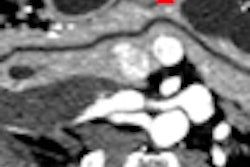

The study evaluated the effectiveness of a low-dose MDCT technique in differentiating breast lesions originally found on mammography or ultrasound scans. The researchers found that breast MDCT had some advantages over breast MRI, another adjunctive breast imaging modality.